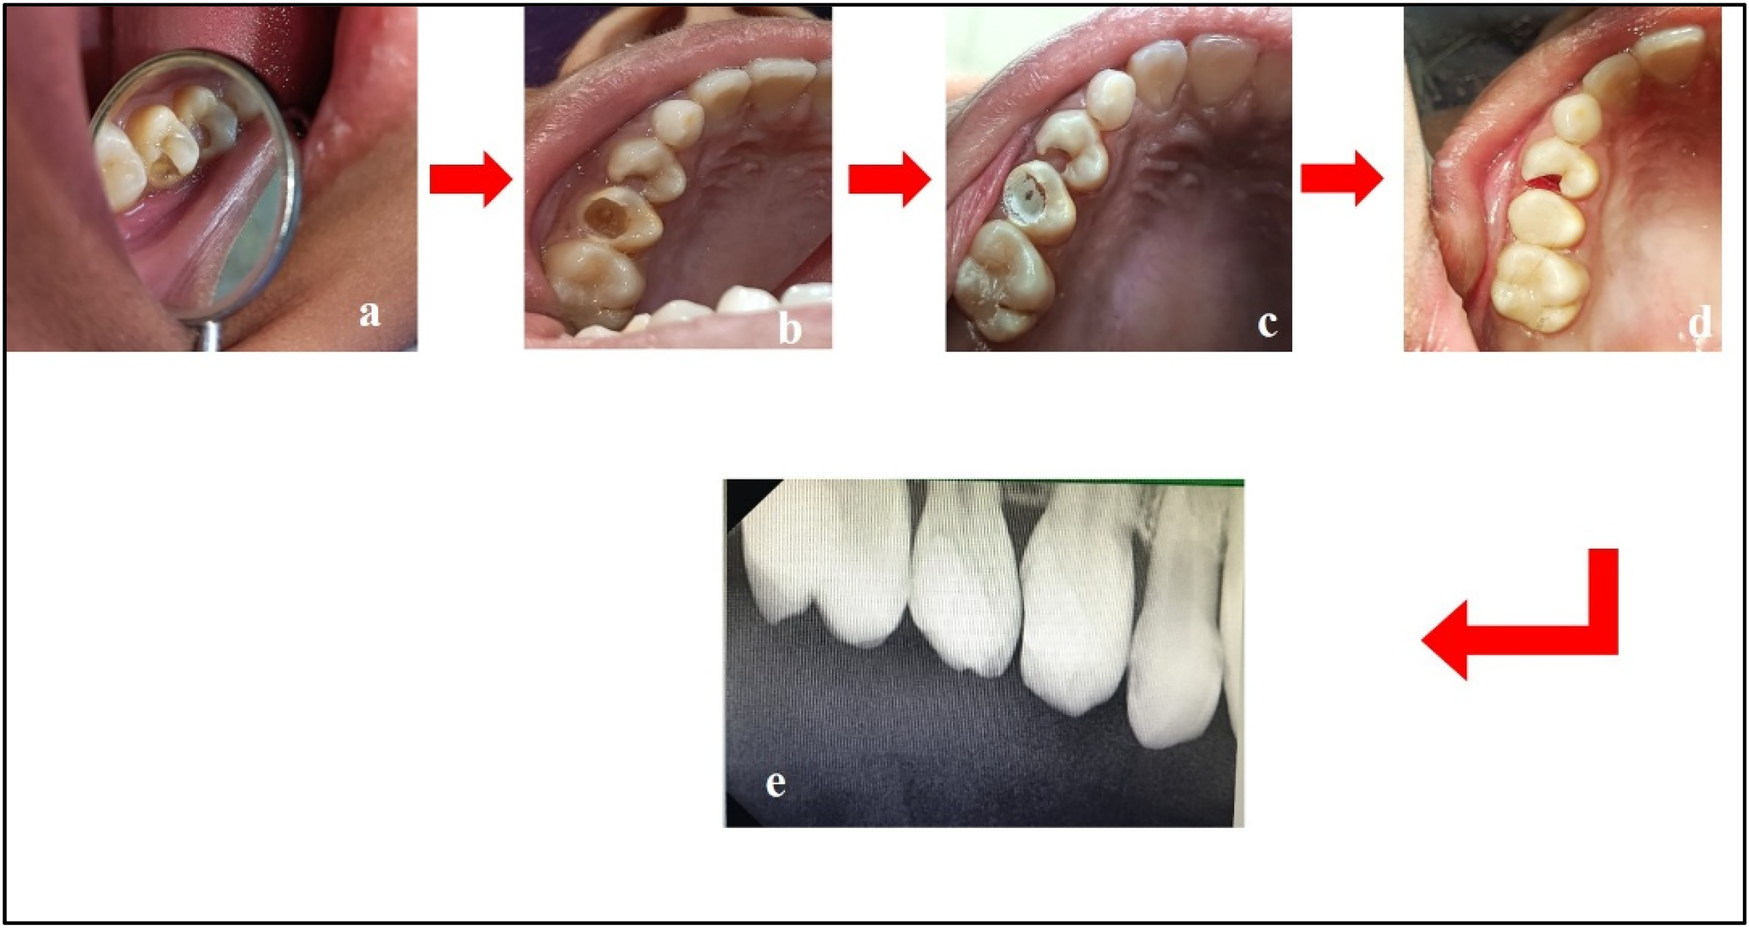

The treatment for PEIR involved surgical removal of the caries, carried out in the following steps (Tables 3–5):

Step 1: Excavation of caries using a round bur [Mani BR 31 carbide round bur (Mani Inc., Tochigi, Japan)] under complete isolation.

Step 2: Placement of Biodentine™.

Step 3: Restoration using Light-Cure Glass Ionomer Cement (LC-GIC).

Figure 5. Treatment done w.r.t. teeth 44 and 45. (a) Caries excavation completed; (b) placement of Biodentine™; and (c) restoration using LC-GIC.

Figure 6. Treatment done w.r.t. teeth 14 and 15. (a) Pre-treatment; (b) caries excavation done w.r.t. tooth 15; (c) placement of Biodentine™ w.r.t. tooth 15; (d) composite restoration w.r.t. tooth 15 and cauterization of gingival polyp w.r.t. tooth 14; (e) post-treatment radiograph w.r.t. teeth 14 and 15.

In this case, we chose to treat conservatively because there was no communication between the lesion and the pulp. Mineral Trioxide Aggregate (MTA) or Biodentine™ is the material of choice for treating such cases. For this case, the chosen material was Biodentine™, which was placed over the decay and followed by LC-GIC as the coronal filling material. In cases of extensive resorption, extraction may be the only viable option, requiring careful treatment planning to address prosthetic or orthodontic needs.